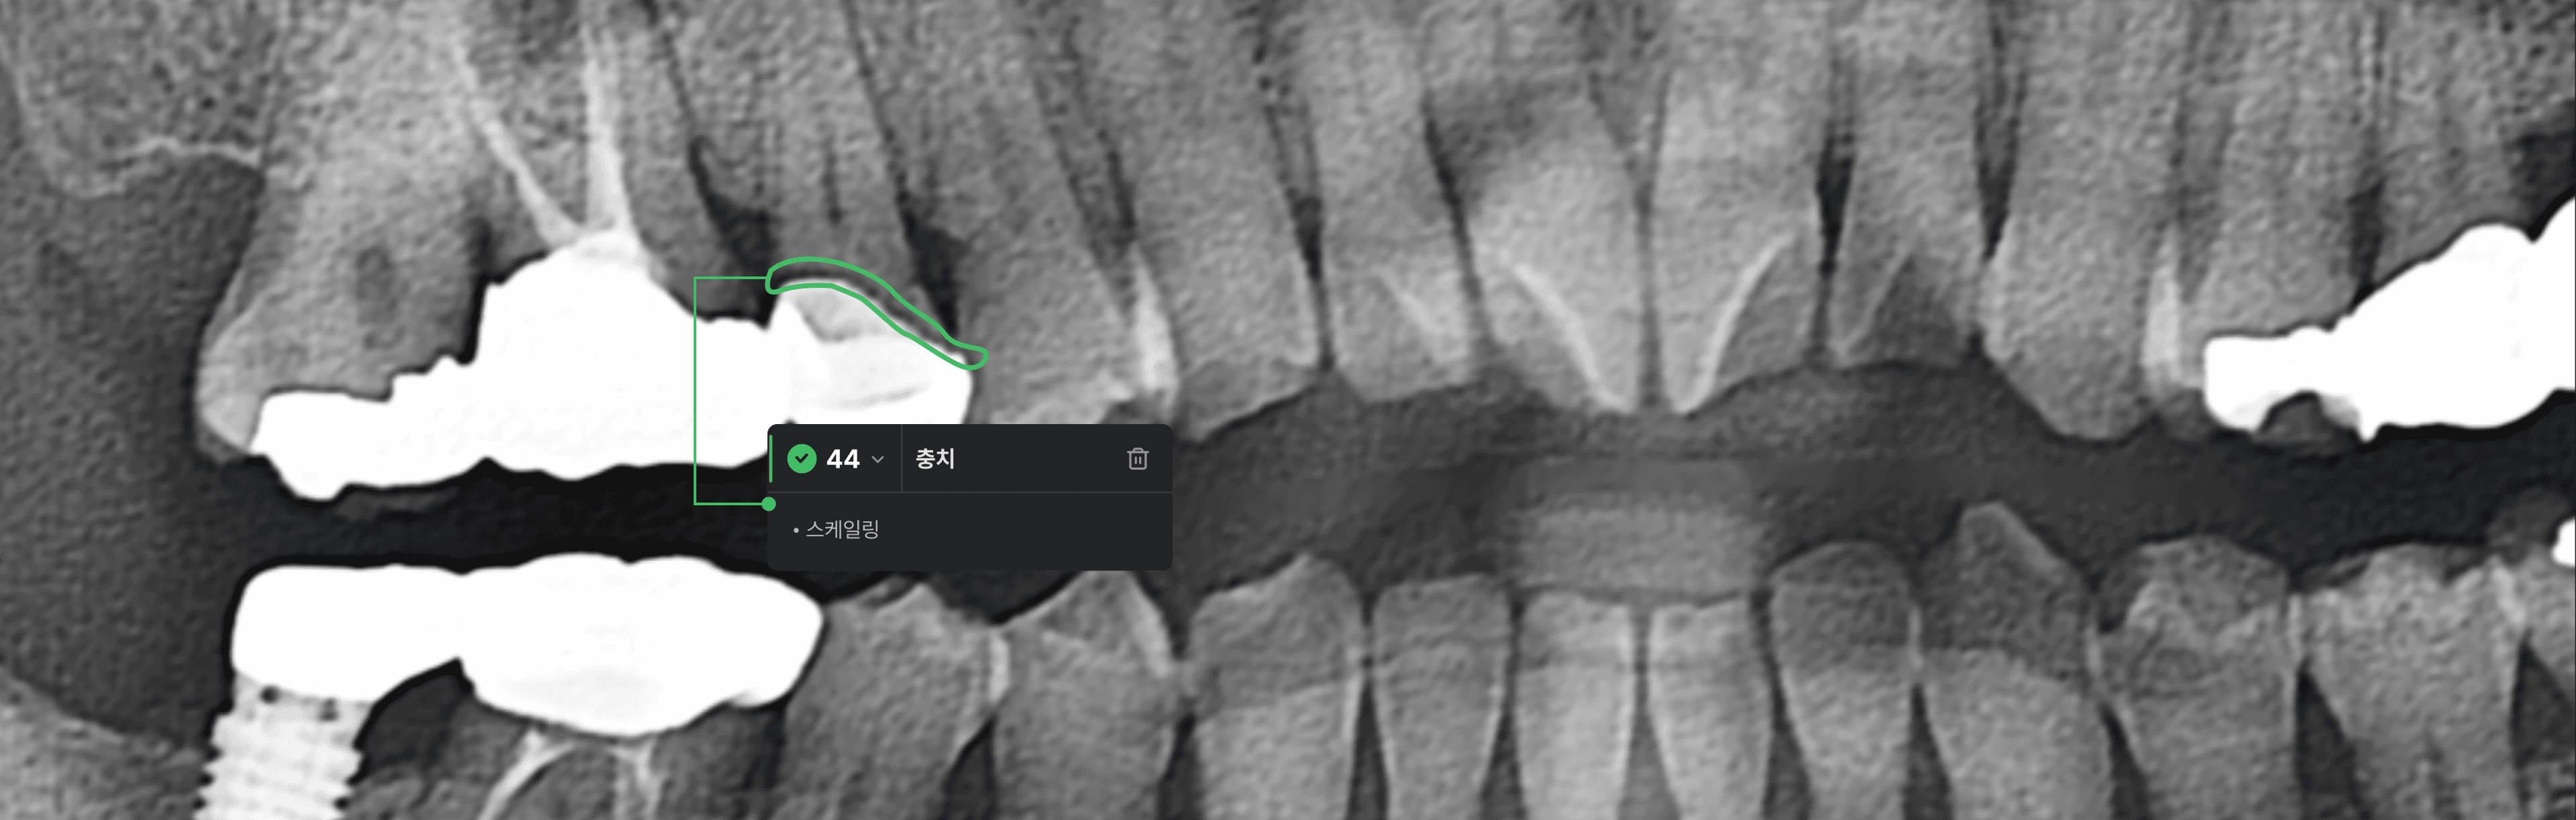

AI 치아정보 탐지

Pano는 인공지능 기술을 활용해 판독시 놓치기 쉬운 세부적인 의심부위를 탐지하고 시각적으로 표기합니다.

치아우식 판독 보조

치아우식증에 대해 1차 판독 은 치과의사 3명이 AI 없이 각 영상을 판독 했고, 2차 판독은 동일 영상을 AI의 도움을 받아 판독하여 F1 score를 산출했습니다.